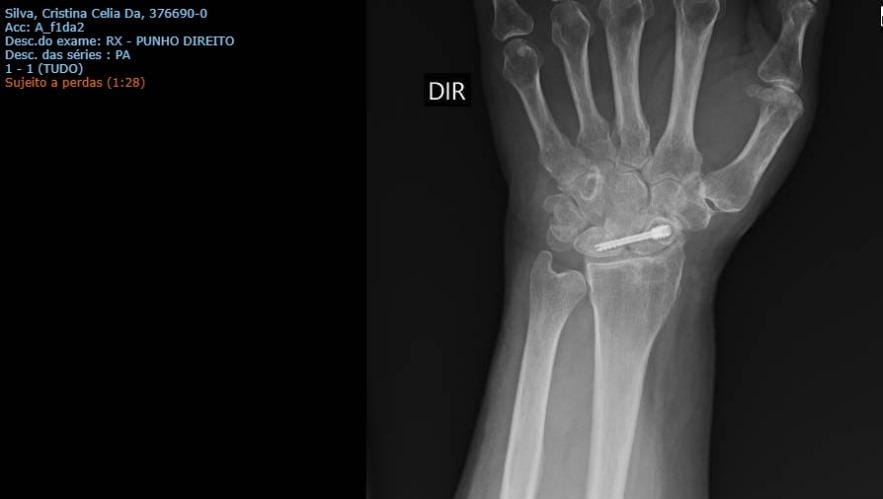

Oie, eu sou a Cris, maquiadora da Riot, e hoje vim pedir uma ajuda para vocês. Preciso realizar uma cirurgia de remoção de um parafuso na minha mão(minha ferramenta de trabalho), mas não tenho o valor para isso. Criei uma vakinha para tentar realizar com a ajuda de vocês.

Segue a imagem do exame apresentando a soltura do parafuso e também o orçamento do cirurgião. Conto com a ajuda de vocês, seja doando ou compartilhando para alcançar mais pessoas. Muito obrigada. Pra quem se sentir mais confortável, segue o meu pix: tinamake.cs@gmail.com